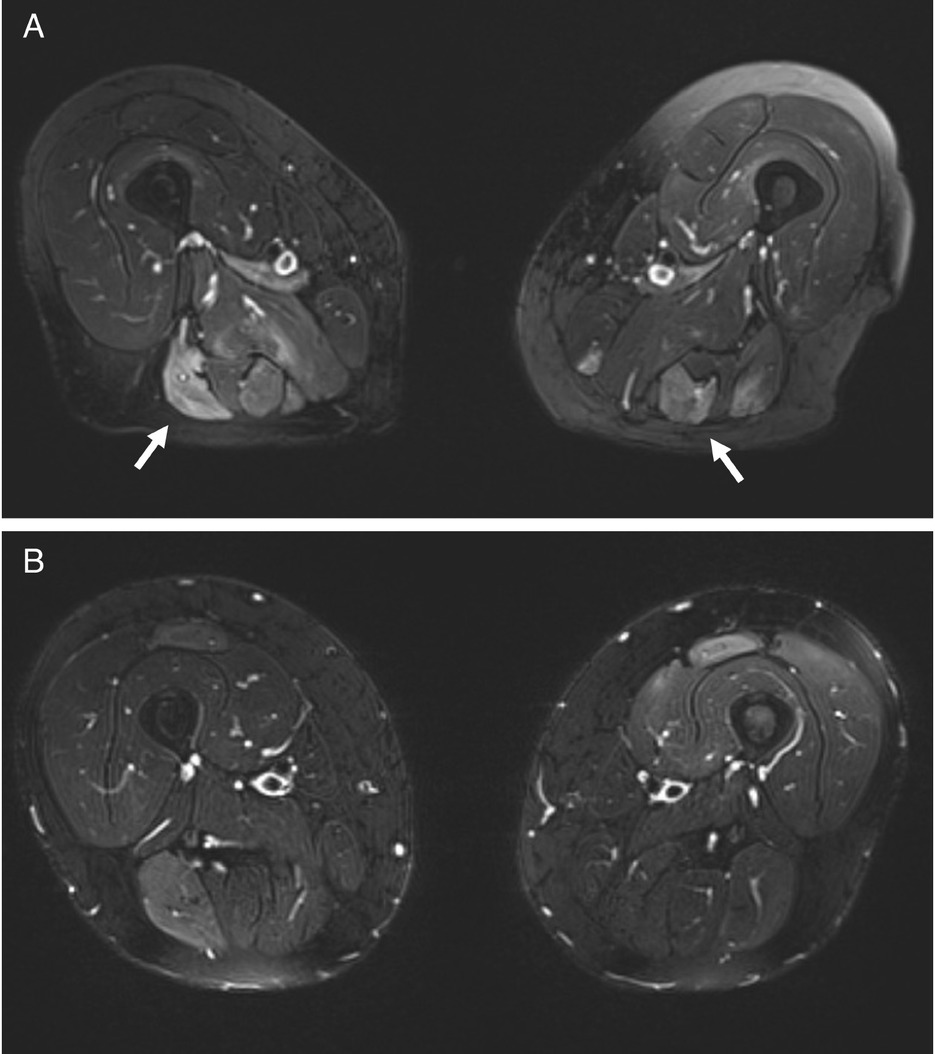

A 57-year-old man (case 1) and a 70-year-old woman (case 2) presented with progressive asthenia and limb muscle weakness. Both showed significantly elevated serum CK levels (12,946 and 11,344 U/L, respectively; reference range 39–308 U/L). Only case 2 had a history of statin use, but both had taken red yeast rice supplements prior to symptom onset. EMG revealed myositic and myopathic changes in both patients. In case 1, magnetic resonance image (MRI) was showed hyperintensities on FAT-suppressed images (Figure 1A). Anti-HMGCR antibodies were strongly positive on an enzyme-linked immunosorbent assay (ELISA) in both cases (315 and 402 U, respectively; reference range < 20 U). Initial treatment included high-dose intravenous steroids and IVIG followed by oral high-dose corticosteroids and MTX, with a rapid CK reduction and progressive improvement of muscle strength. However, CK and anti-HMGCR antibody levels remained elevated, and symptoms persisted, especially in case 1. In this patient a muscle biopsy was performed and discrete inhomogeneity in fibres calibre, nuclear internalizations, isolated nicotinamide adenine dinucleotide (NADH)-positive hypotrophic and diverse regenerating fibres, diffuse modest CD68 expression and increased expression of membrane attack complex (MAC) and major histocompatibility complex (MHC) class I on cellular surfaces in a picture of myopathic damage were found. For this reason, RTX therapy was proposed (1000 mg two weeks apart and then every 6 months for 3 times). Following RTX therapy, case 1 achieved full recovery, with normalization of CK, complete negativization of anti-HMGCR antibodies, resolution of MRI findings, and discontinuation of IVIG (Figure 1B, 2A-B). No adverse events occurred during and after treatment. Case 2 improved clinically, discontinued MTX and IVIG, and achieved reduction of anti-HMGCR antibody levels (Figure 2C-D). In this patient, a mild IgG1 deficiency occurred after RTX, without increased infections.

MRI scans of the thighs before and after rituximab therapy in Case 1. (A) Axial T2-weighted images of the upper thigh (December 2020) showing extensive areas of hyperintensity with muscle edema (white arrows). (B) Follow-up axial T2-weighted images (May 2022) of the same region demonstrate marked resolution of the previously observed edema.